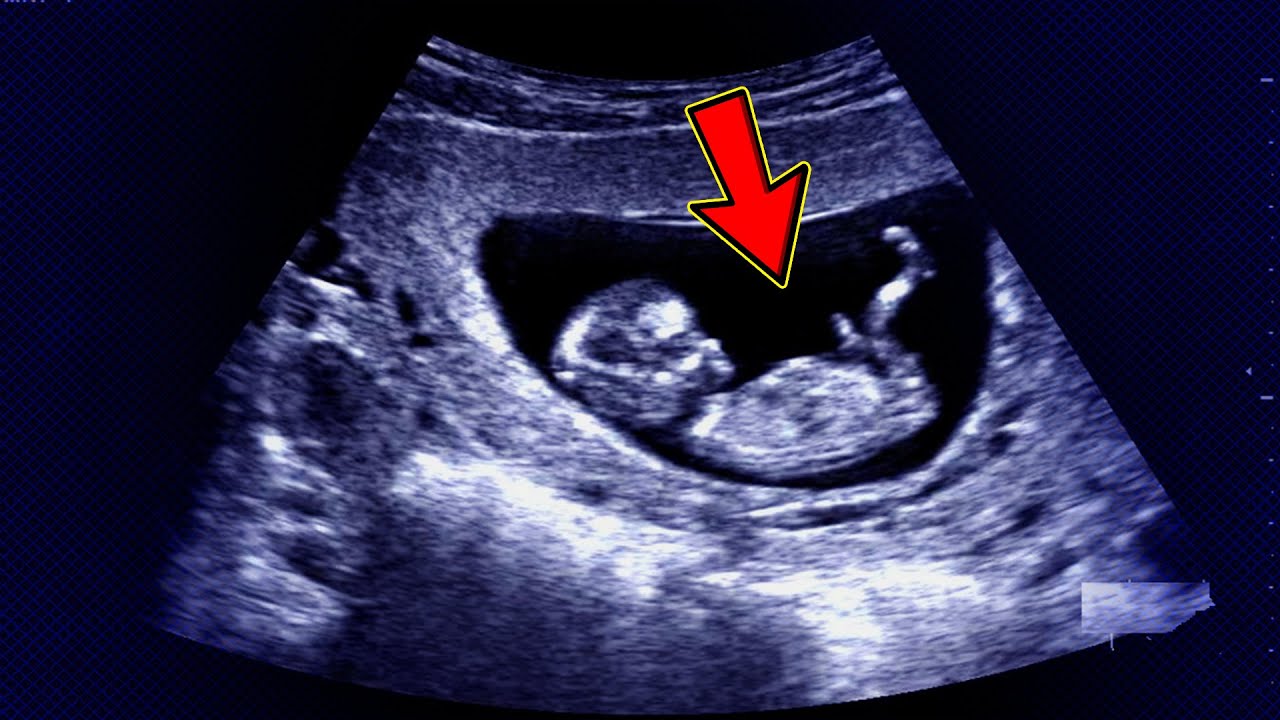

• الموجات فوق الصوتية: يتم وضع محول طاقة على بطن الأم وتعمل الموجات الصوتية على تكون صورة للجنين في أحشائها ويمكن قياس معدل نبضات القلب عن طريق النظر إلى صورة الموجات الفوق صوتية، وتُعد هذه الطريقة هي الطريقة الأكثر شيوعًا لمعرفة نبضات قلب الجنين.